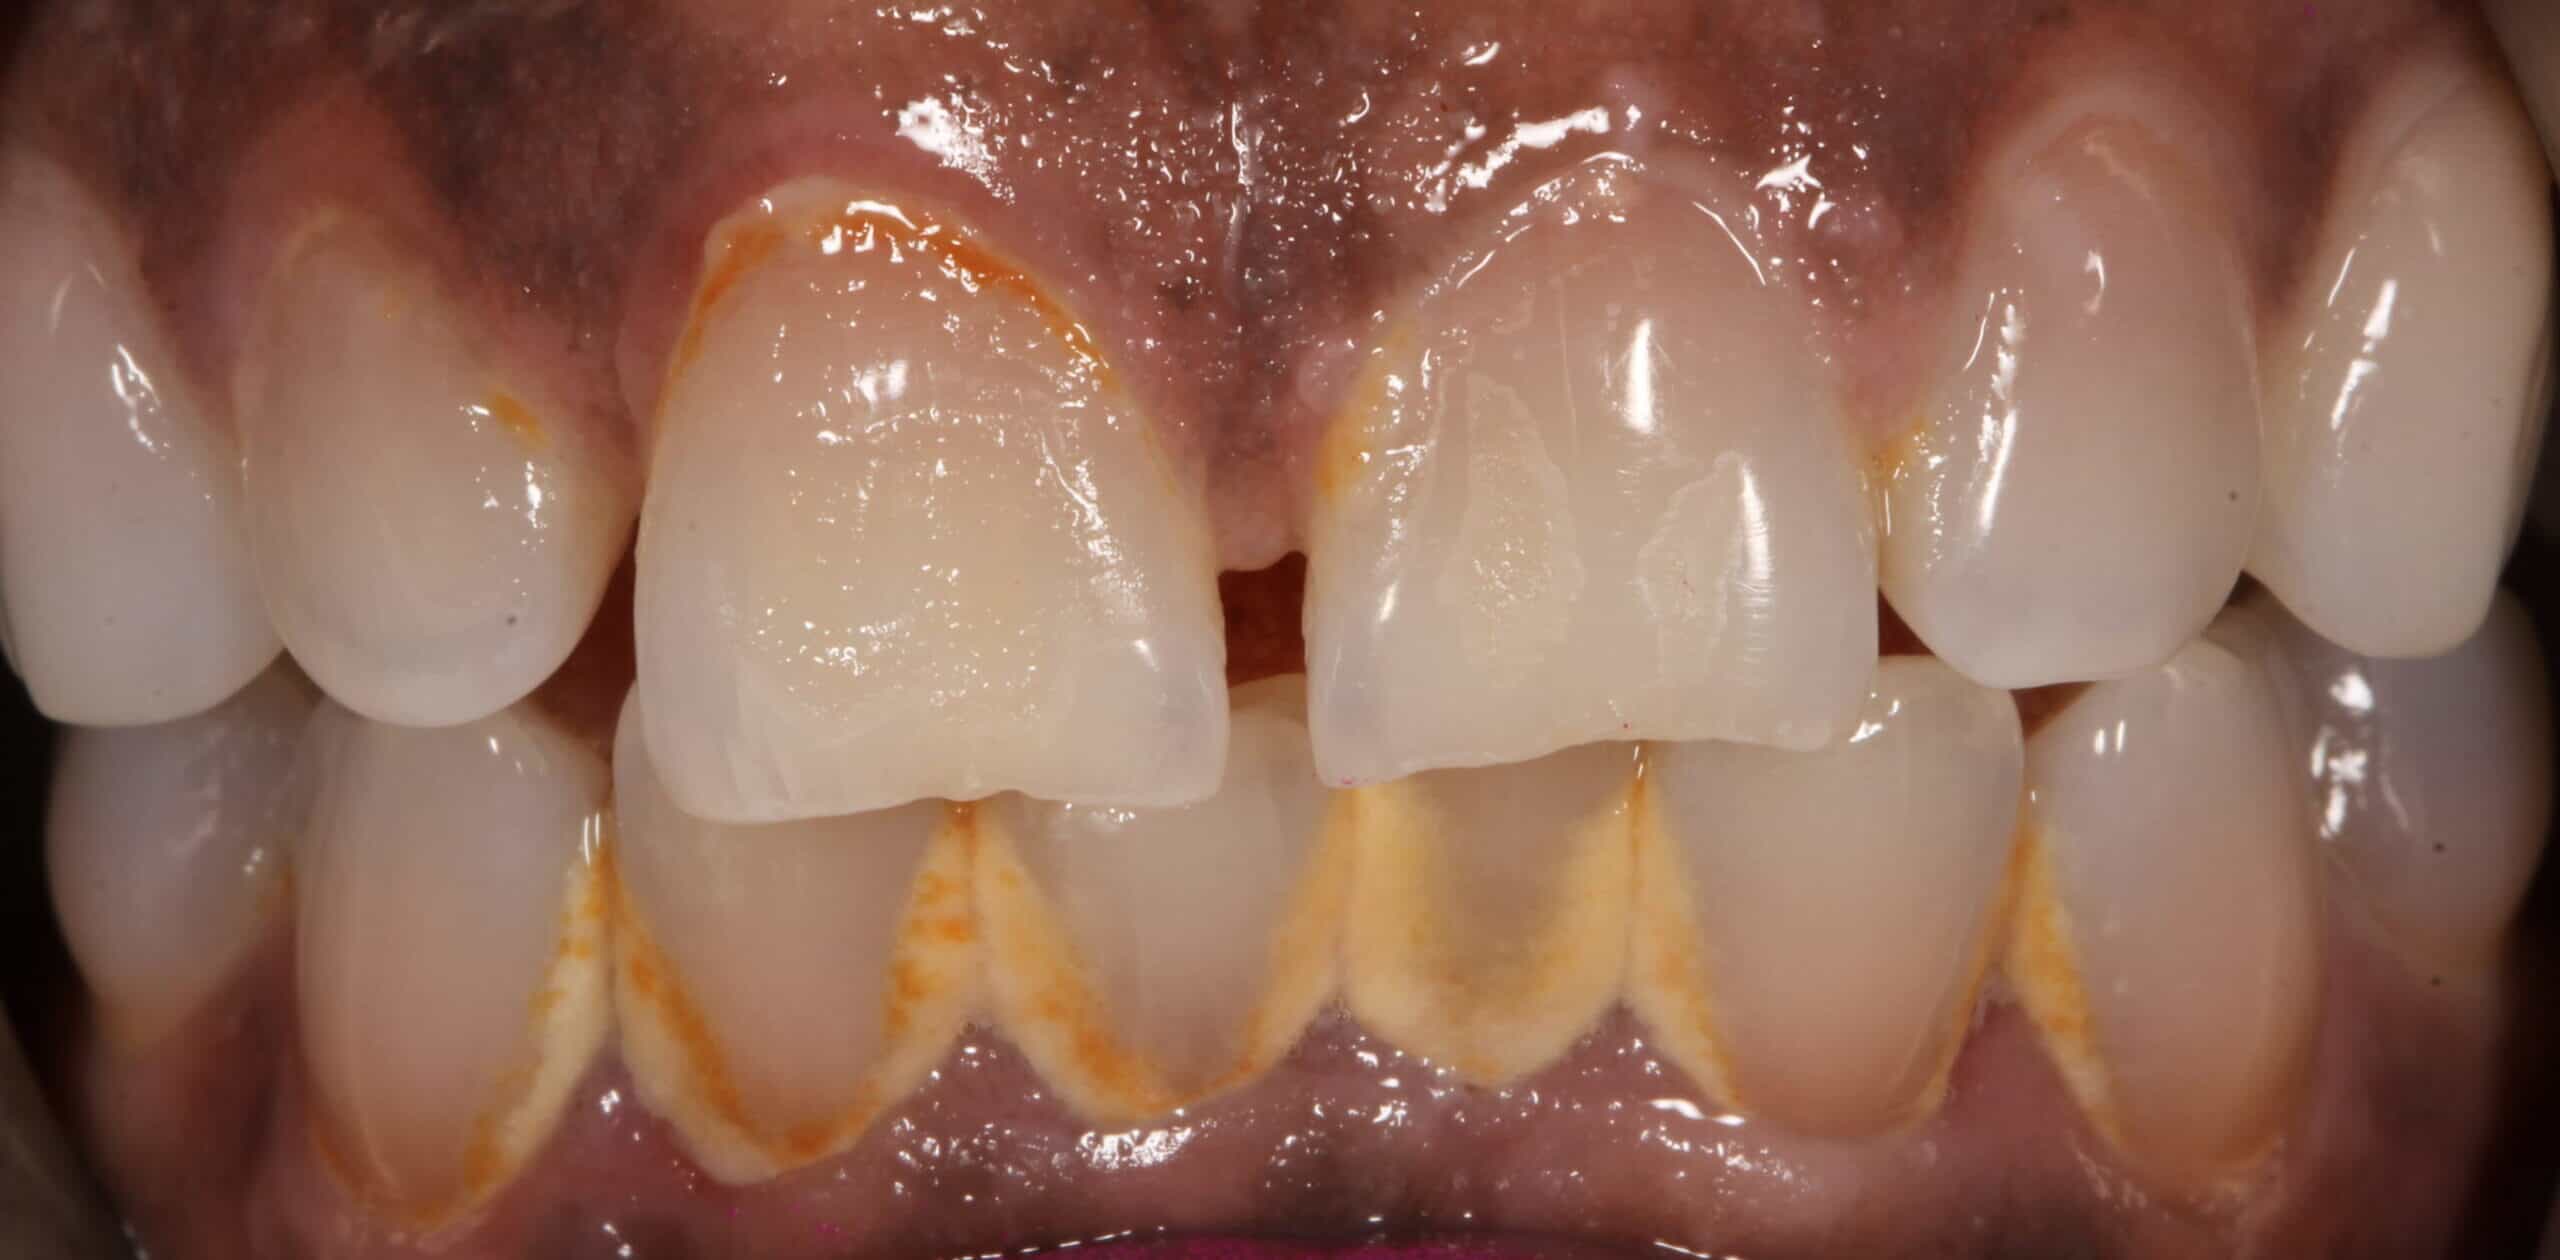

Does teeth cleaning remove yellow?

Your teeth will certainly look brighter and whiter after a deep clean, because tartar build-up takes on a yellowish hue. As the removal of plaque and tartar is a primary focus of the procedure, it will have an immediate positive effect on the overall look of your smile. However, if you’re looking for markedly whiter results you’ll need to book in for a whitening treatment in order to achieve them. Tooth whitening is one of the easiest and most popular cosmetic dentistry procedures we offer, and the results can be nothing short of dramatic.

Your teeth may, indeed, feel a little looser after having a deep clean, but this is definitely nothing to worry about. When the build-up of plaque and tartar is removed from in between individual teeth, naturally there is a space where it has been accommodated – in some cases, a heavy buildup has been gathering over a long period of time. The feeling of looseness shouldn’t be seen as a problem, however, and while it might take a little getting used to, it’s actually a sign the procedure has been of benefit.